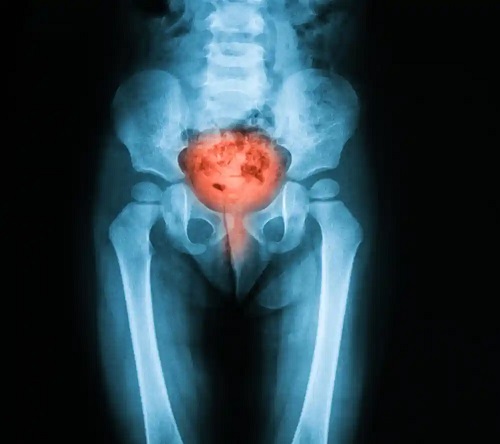

Cistoscopia este o procedură chirurgicală care permite explorarea vezicii urinare , a uretrei și a orificiilor dinspre uretere. Acestea din urmă sunt tuburile prin care urina trece de la rinichi în vezică. Manevra se efectuează cu un instrument numit cistoscop.

- Investigarea cauzelor anumitor semne sau simptome. Cistoscopia poate ajuta la stabilirea cauzei unor probleme cum ar fi incontinența, durerea la urinare, vezica urinară hiperactivă și hematuria sau sângele în urină.